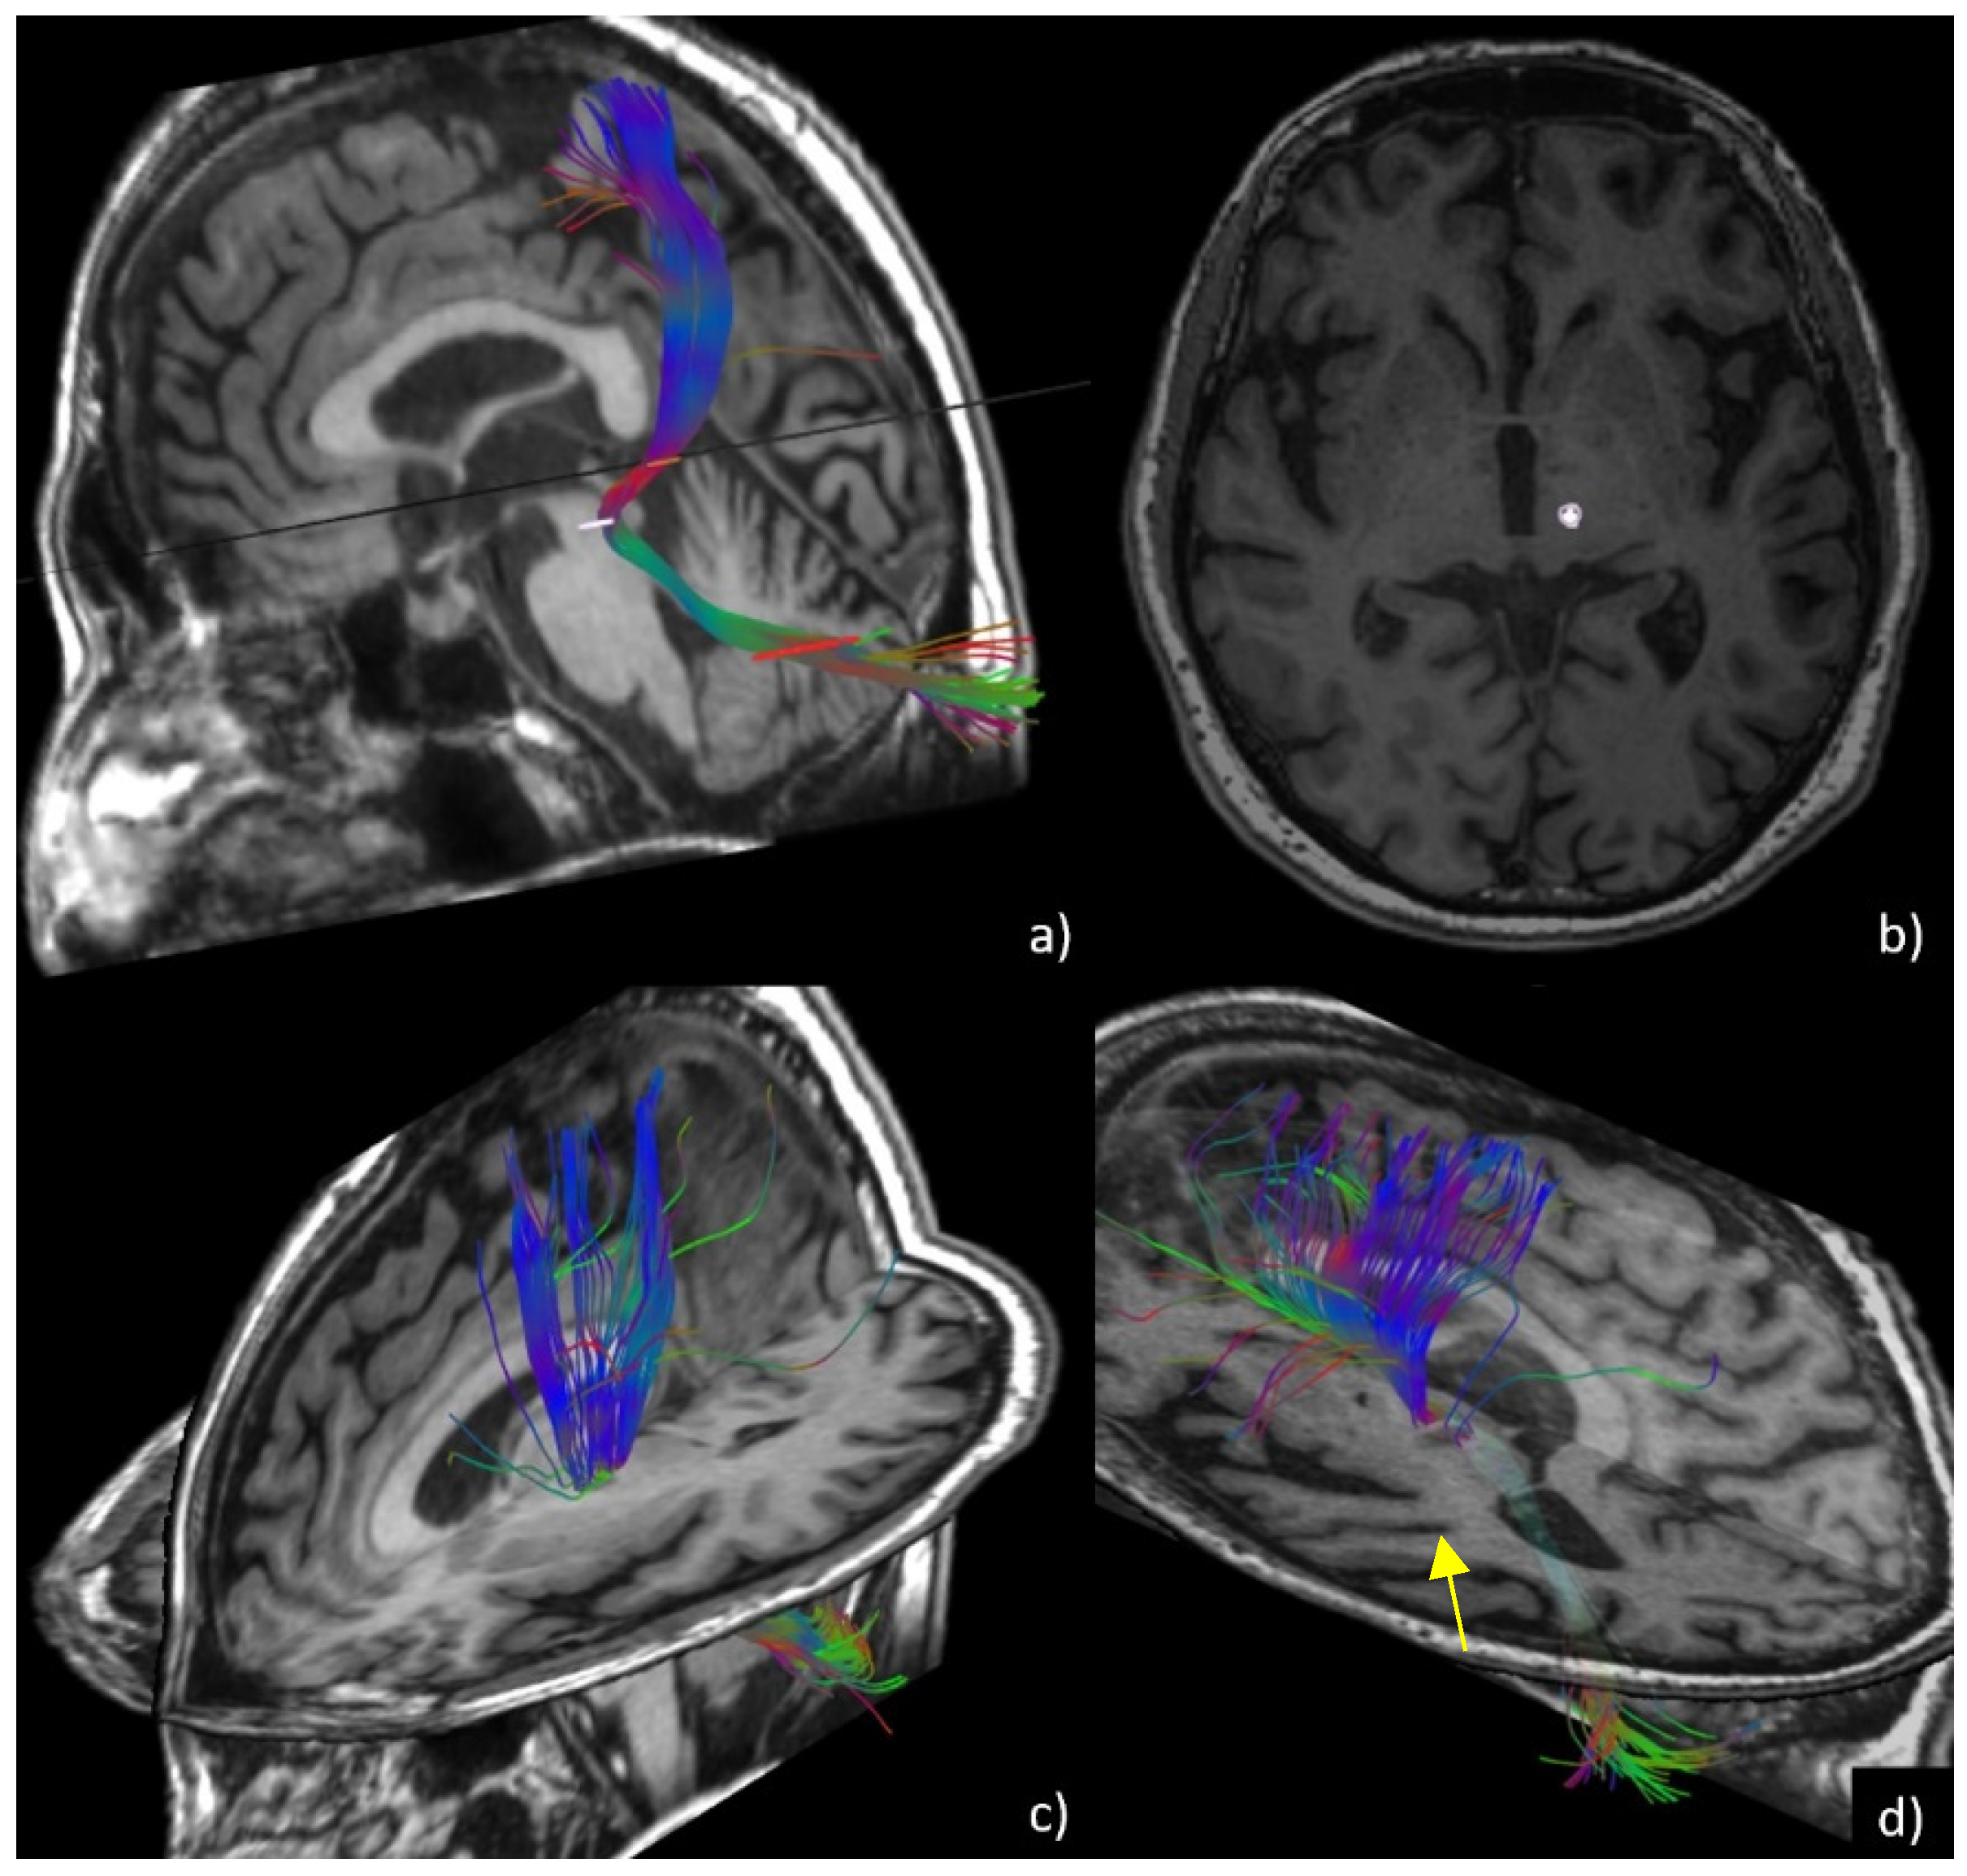

- Tractography evaluation of the dentato-rubro-thalamic tract (DRTt) before and six months after treatment. DTI sequences were acquired using the following parameters: 33 diffusion directions, TR 5700 ms, TE 98 ms, parallel imaging (acceleration factor two), 3 mm slice thickness, 39 slices, matrix 128 × 128, 230 mm FOV, b value 1000 s/mm2, acquisition time 4:01 min. A T1-weighted 3D IR FSPGR BRAVO sequence with multiplanar reconstructions was also acquired (parameters: FOV 24, slice thickness 1.6 mm, flip angle 20°, prep time 450, TE 3.2, matrix 256 × 192, NEX 3, duration 13 min). Probabilistic fiber tracking was performed using a dedicated software (Brainance MD, Advantis Medical Imaging, Eindhoven, NL). An EPI correction tool for distortion correction was applied before image analysis. The fractional anisotropy threshold was set at 0.15, minimum fiber length 0 mm, maximum fiber length 200 mm, angular threshold 27°, and step size 1 mm. The dentato-rubro-thalamic tract (DRTt) was obtained by manual definition of the following three regions of interest (ROIs) on axial images, as described in previous experiments [21]: the cerebellar dentate nucleus ipsilateral to the target, the ipsilateral red nucleus, and the supposed location of the ipsilateral Vim at the level of the thalamus on the AC-PC plane. We evaluated whether the bundle was eccentric or central with respect to the thalamotomy lesion using post-procedural images six months after treatment. Similar to the methods described by Miller et al. [9], the two neuroradiologists measured the amount of overlap between the thalamotomy lesions and the DRTts and classified the bundle position as central (overlap > 50%) or eccentric (overlap < 50%). Moreover, ADC and FA values at the thalamotomy level were measured using the ROI previously set for DRTt tractography (Figure 1).